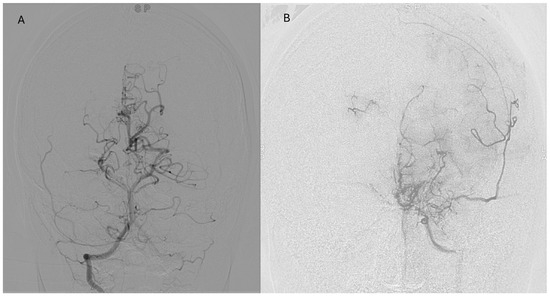

Representative postoperative angiographic images are shown in Figure 1, Figure 2 and Figure 3. The mean operative time was 3.2 h and the average length of hospital stay was 7 days. All patients were monitored in the pediatric intensive care unit for 24–48 h before being transferred to the ward.

Figure 2. Postoperative anteroposterior DSA of the right vertebral artery (A) and left ICA (B) following pial synangiosis using the superficial temporal artery as a donor vessel. The images demonstrate robust ingrowth of transdural collaterals. Notably, there is visualization of external carotid artery (ECA) to ICA collaterals arising from the middle meningeal and superficial temporal arteries. These findings are consistent with Moyamoya disease involving posterior circulation. DSA: digital subtraction angiography; ECA: external carotid artery; ICA: internal carotid artery.